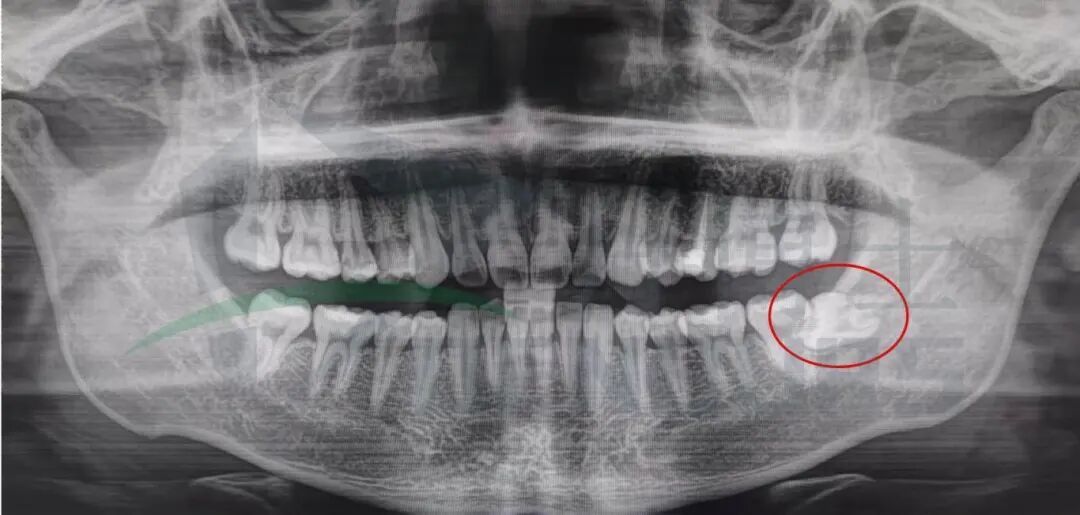

影像学检查

全景片显示:38近中水平高位阻生,37远中邻面部分透射影。